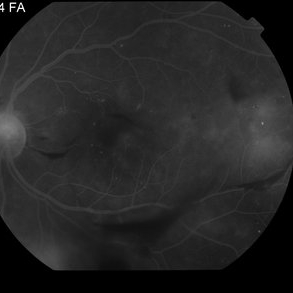

Proliferative Diabetic Retinopathy with Vitreous Hemorrhage - FA late

Oct 18 2012 by Suber S. Huang, MD, MBA, FASRS

30 year old diabetic man with proliferative diabetic retinopathy and vitreous hemorrhage

Photographer: Stacie Hrvatin

Condition/keywords: cotton wool spots, neovascularization (NV), subhyaloid hemorrhage, vitreous hemorrhage